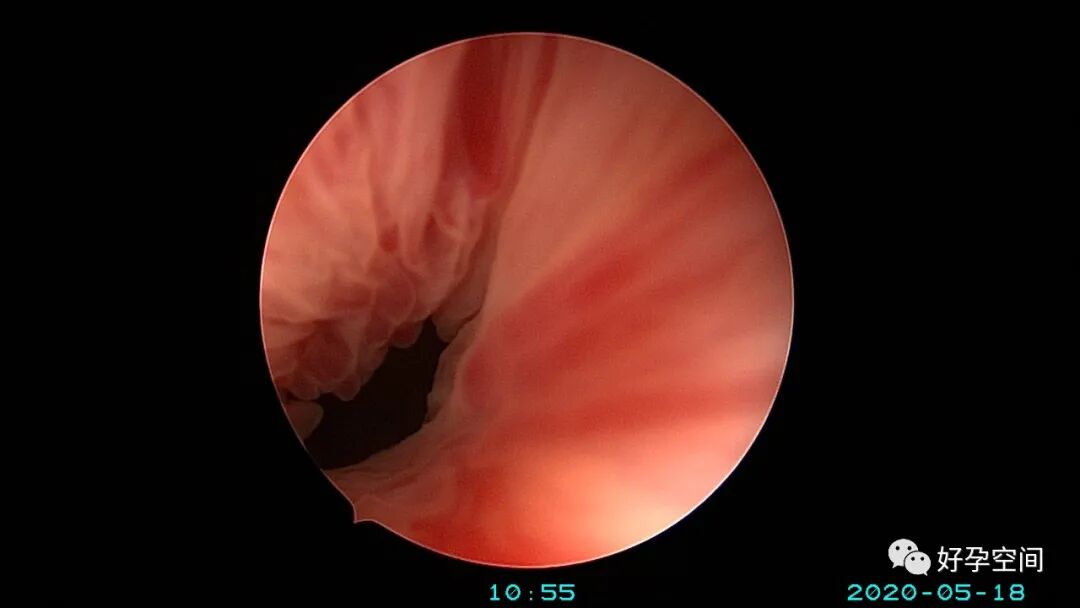

病例3:(病人年龄及取卵个数不详)取卵术后血尿膀胱内血块尿潴留,膀胱灌洗效果不佳,宫腔镜探查膀胱,清除血块,膀胱多处穿刺伤,电凝止血。

病例4:32岁,取卵13枚,取卵术后血尿膀胱内血块尿潴留,膀胱灌洗效果不佳,宫腔镜探查膀胱,清除血块,膀胱底见穿刺伤,电凝止血。